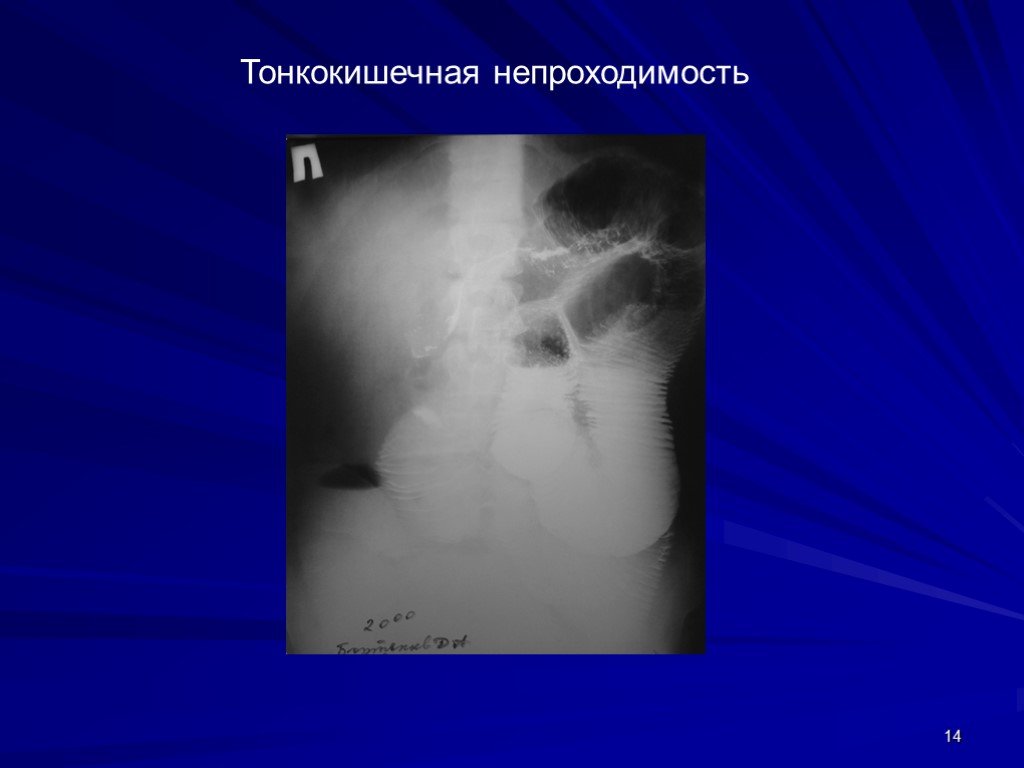

Иллюстрации и информация о симптомах острого кишечного непроходимости